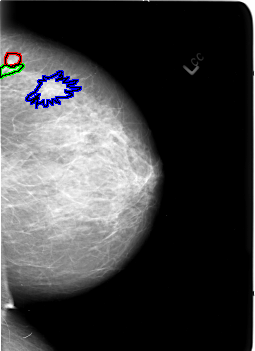

FILE: B_3029_1.LEFT_CC.OVERLAY

TOTAL_ABNORMALITIES 3

ABNORMALITY 1

LESION_TYPE MASS SHAPE ROUND MARGINS CIRCUMSCRIBED

ASSESSMENT 3

SUBTLETY 3

PATHOLOGY BENIGN

TOTAL_OUTLINES 1

BOUNDARY

ABNORMALITY 2

LESION_TYPE CALCIFICATION TYPE PLEOMORPHIC DISTRIBUTION LINEAR-SEGMENTAL

ASSESSMENT 4

PATHOLOGY MALIGNANT

ABNORMALITY 3

LESION_TYPE MASS SHAPE ARCHITECTURAL_DISTORTION MARGINS N/A

SUBTLETY 2